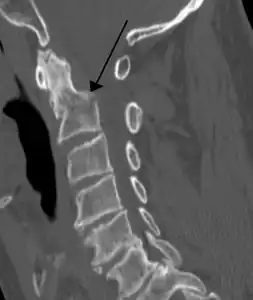

Radiographic detection

On CT scan or X-ray, a cervical fracture may be directly visualized. In addition, indirect signs of injury by the vertebral column are incongruities of the vertebral lines,[7] and/or increased thickness of the prevertebral space:[8]

X-ray of normal congruous vertebral lines